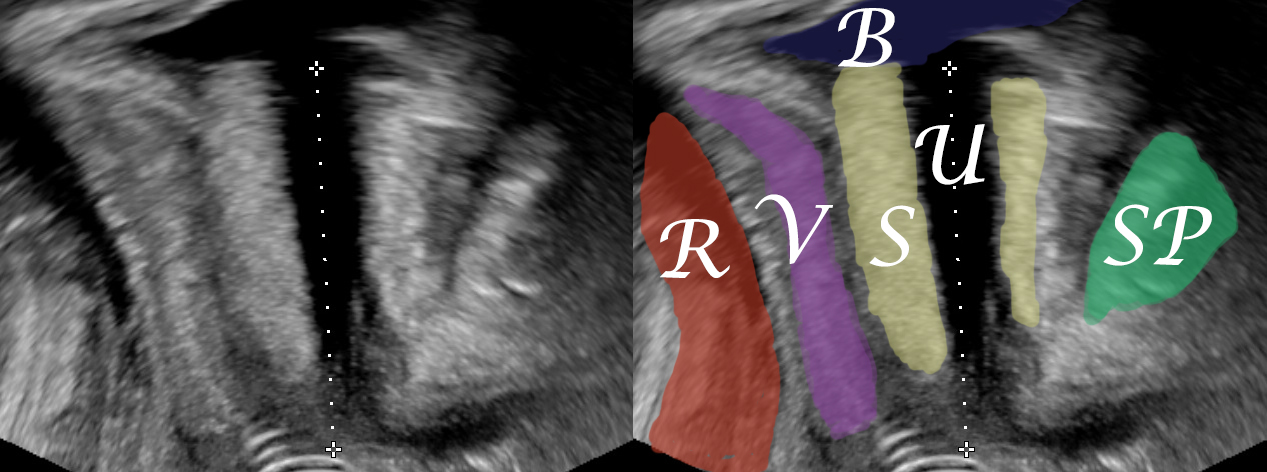

A median sagittal image of the urethra should be achieved with the ultrasound probe placed on the external urethral meatus. The pubic symphysis should be on the right as a reference point. Care should be taken that no pressure is applied on the urethra, something that would lead to a measurement shorter than the true urethral length. Thus there should be adequate distance between the ultrasound probe and the urethral sphincter complex. The urethral length is measured along the anechoic urethra (Wlazlak E et al, 2016).